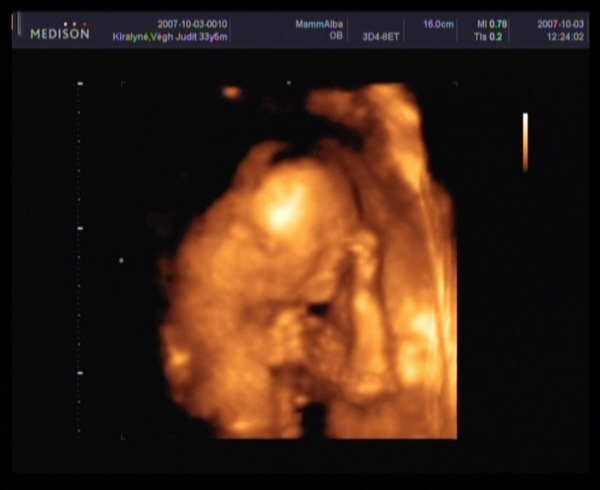

Megjöttem a 4D-ről.

Szupi volt, bár sajna kicsi bogaram állandóan vagy a néhlepénybe furta az arcát, vagy a kezecskéit tette az arcocskája elé, és elég nehéz volt rendesen elkapni.

Azt is mondta a doki, hogy nagyon mélyen fekszik, és ez is okozhatja azt, hogy ilyen későn kezdtem el érezni.

Amugy minden rendben van, 20 hetesnek megfelelő.

És végre a lábaközét is megmutatta nekünk.

Ha jól látom az első képet, (nem biztos) akkor PÖCSÖS!!!!!!!!!

Szerintem kislány!Én látom a szoknyáját :lol: :lol: :lol: :lol: